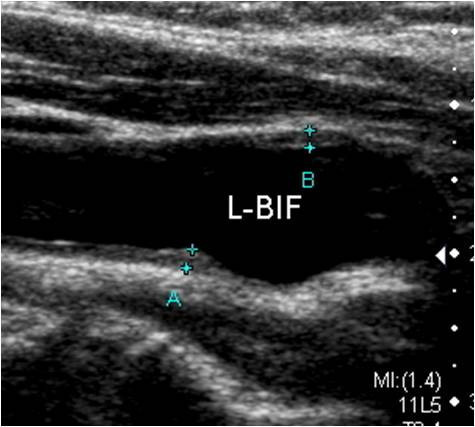

- 혈관 내막-중막 두께(IMT, Intima-Media Thickness) 증가: 동맥경화의 초기 단계에서 관찰되는 변화로, 심혈관계 질환 위험을 예측하는 주요 지표로 활용됩니다.

- IMT 0.9mm 이하: 정상 범위로 판단

- IMT 1.0mm 이상: 동맥경화 진행 가능성 있음

결과지에는 혈류 속도, 혈류 방향, 플라크의 형태 및 위치 등이 함께 기재됩니다. 영상 분석을 통해 플라크의 안정성 여부를 평가하면 향후 뇌졸중 위험 예측에도 도움이 됩니다.